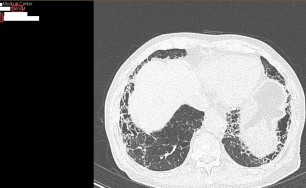

한약이 폐에서 항산화 작용을 하고, 염증관련 신호조절(항염증)을 한다는 연구논문입니다.

숨케어한의원에서는 전화예약을 받고 있습니다. 내원시 엑스레이, CT사진, 폐기능검사지를 가지고 오시면 자세한 상담이 가능합니다.